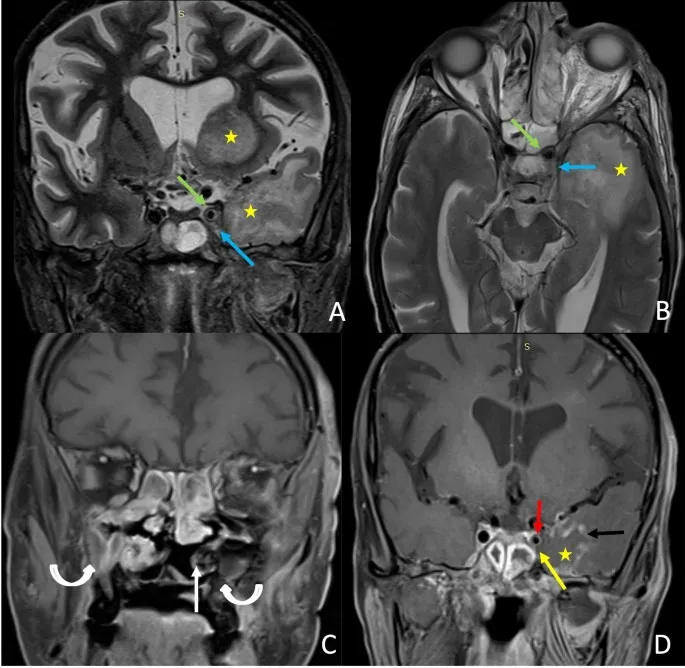

- CECT: Details bone erosion, tumor extent.

- MRI: Assesses soft tissue, perineural spread, intracranial extension.